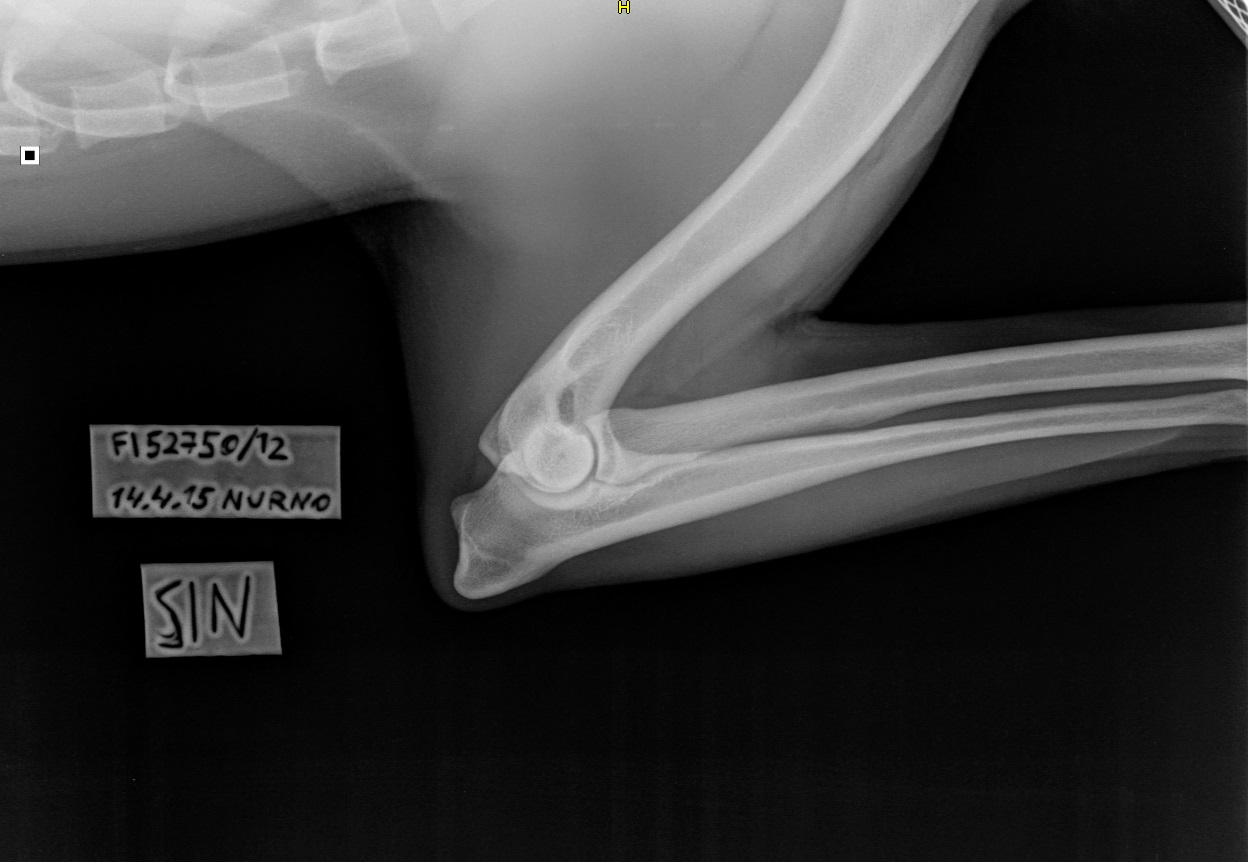

Mosse oli jumissa, lantion alue oli hyvin jumissa ja nikamia oli miten sattuu, selkäranka oli voimakkaasti kaarella ja koko selkä oli hyvin jäykkä ja joustamaton. No jälkikäteen ajateltuna kyllähän Mosse kävelikin vähän kuin vanha vaari mutta eipä sitä muutosta niin huomaa kun tapahtuu pikkuhiljaa. Hierojan jälkeen murinat vähän väheni muttei loppunut kokonaan. Välillä ajattelin että homma johtuu hormoneista ja välillä oltiin niin epäonnistuttu koko koiran kanssa ja sitten taas ajateltiin että koira on kipeä. Hieroja suositteli osteopaattia, mutta aikoja ei niin vain saatukkaan, joten päätettiin kuvauttaa selkä. Ja samalla lonkat ja kyynärät. Selässä ei ollut merkkejä LTVstä eikä muustakaan viasta. Ainut poikkeama oli rintarangan 8.nikamassa näkyvä lovi, hyvin selvästi havaittavissa. Lääkäri ei osannut sanoa olisiko kyseessä "valuvirhe" vai onko voinut aiheutua jostain törmäyksestä tai muusta. Lovi kuitenkin oli sellaisessa paikassa ettei pitäisi haitata elämää millään tavalla. Toinen huomio oli Mossen lantio. Se on vino. Siitäkään ei tullut muuta tuomiota kuin että se nyt vaan on vino. Kun kuvassa selkäranka on suora, on lantio vino ja kun lantio on suora on selkä vinossa. Lonkista ja kyynäristä ei eläinlääkäri antanut mitään arviota, sanoi että tulee sitten kennelliitosta kun tulee. Ja niin tuli A/A ja 0/0.

| Tässä kuvassa näkyy myös tuo lantion vinous |